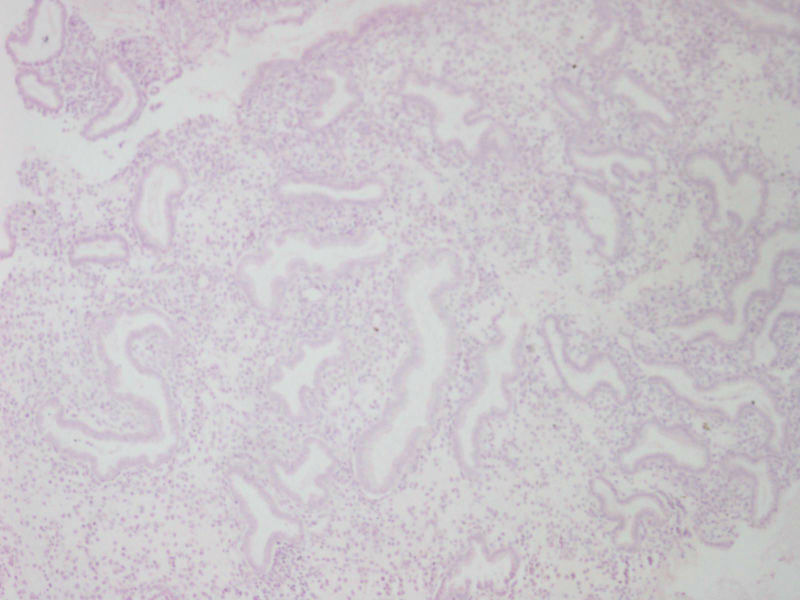

35反复腰腹胀痛伴白带异常1年加重3LMP109,送检日期1021

• 宫内膜图2

图2

子宫内膜不规则增生

分泌期宫内膜

分泌期改变子宫内膜

片子做得太差了,和我们科有一拼了。感觉宫内膜呈分泌期改变

分泌期子宫内膜

分泌期宫内膜,间质有慢性炎细胞浸润

分泌期子宫内膜像。